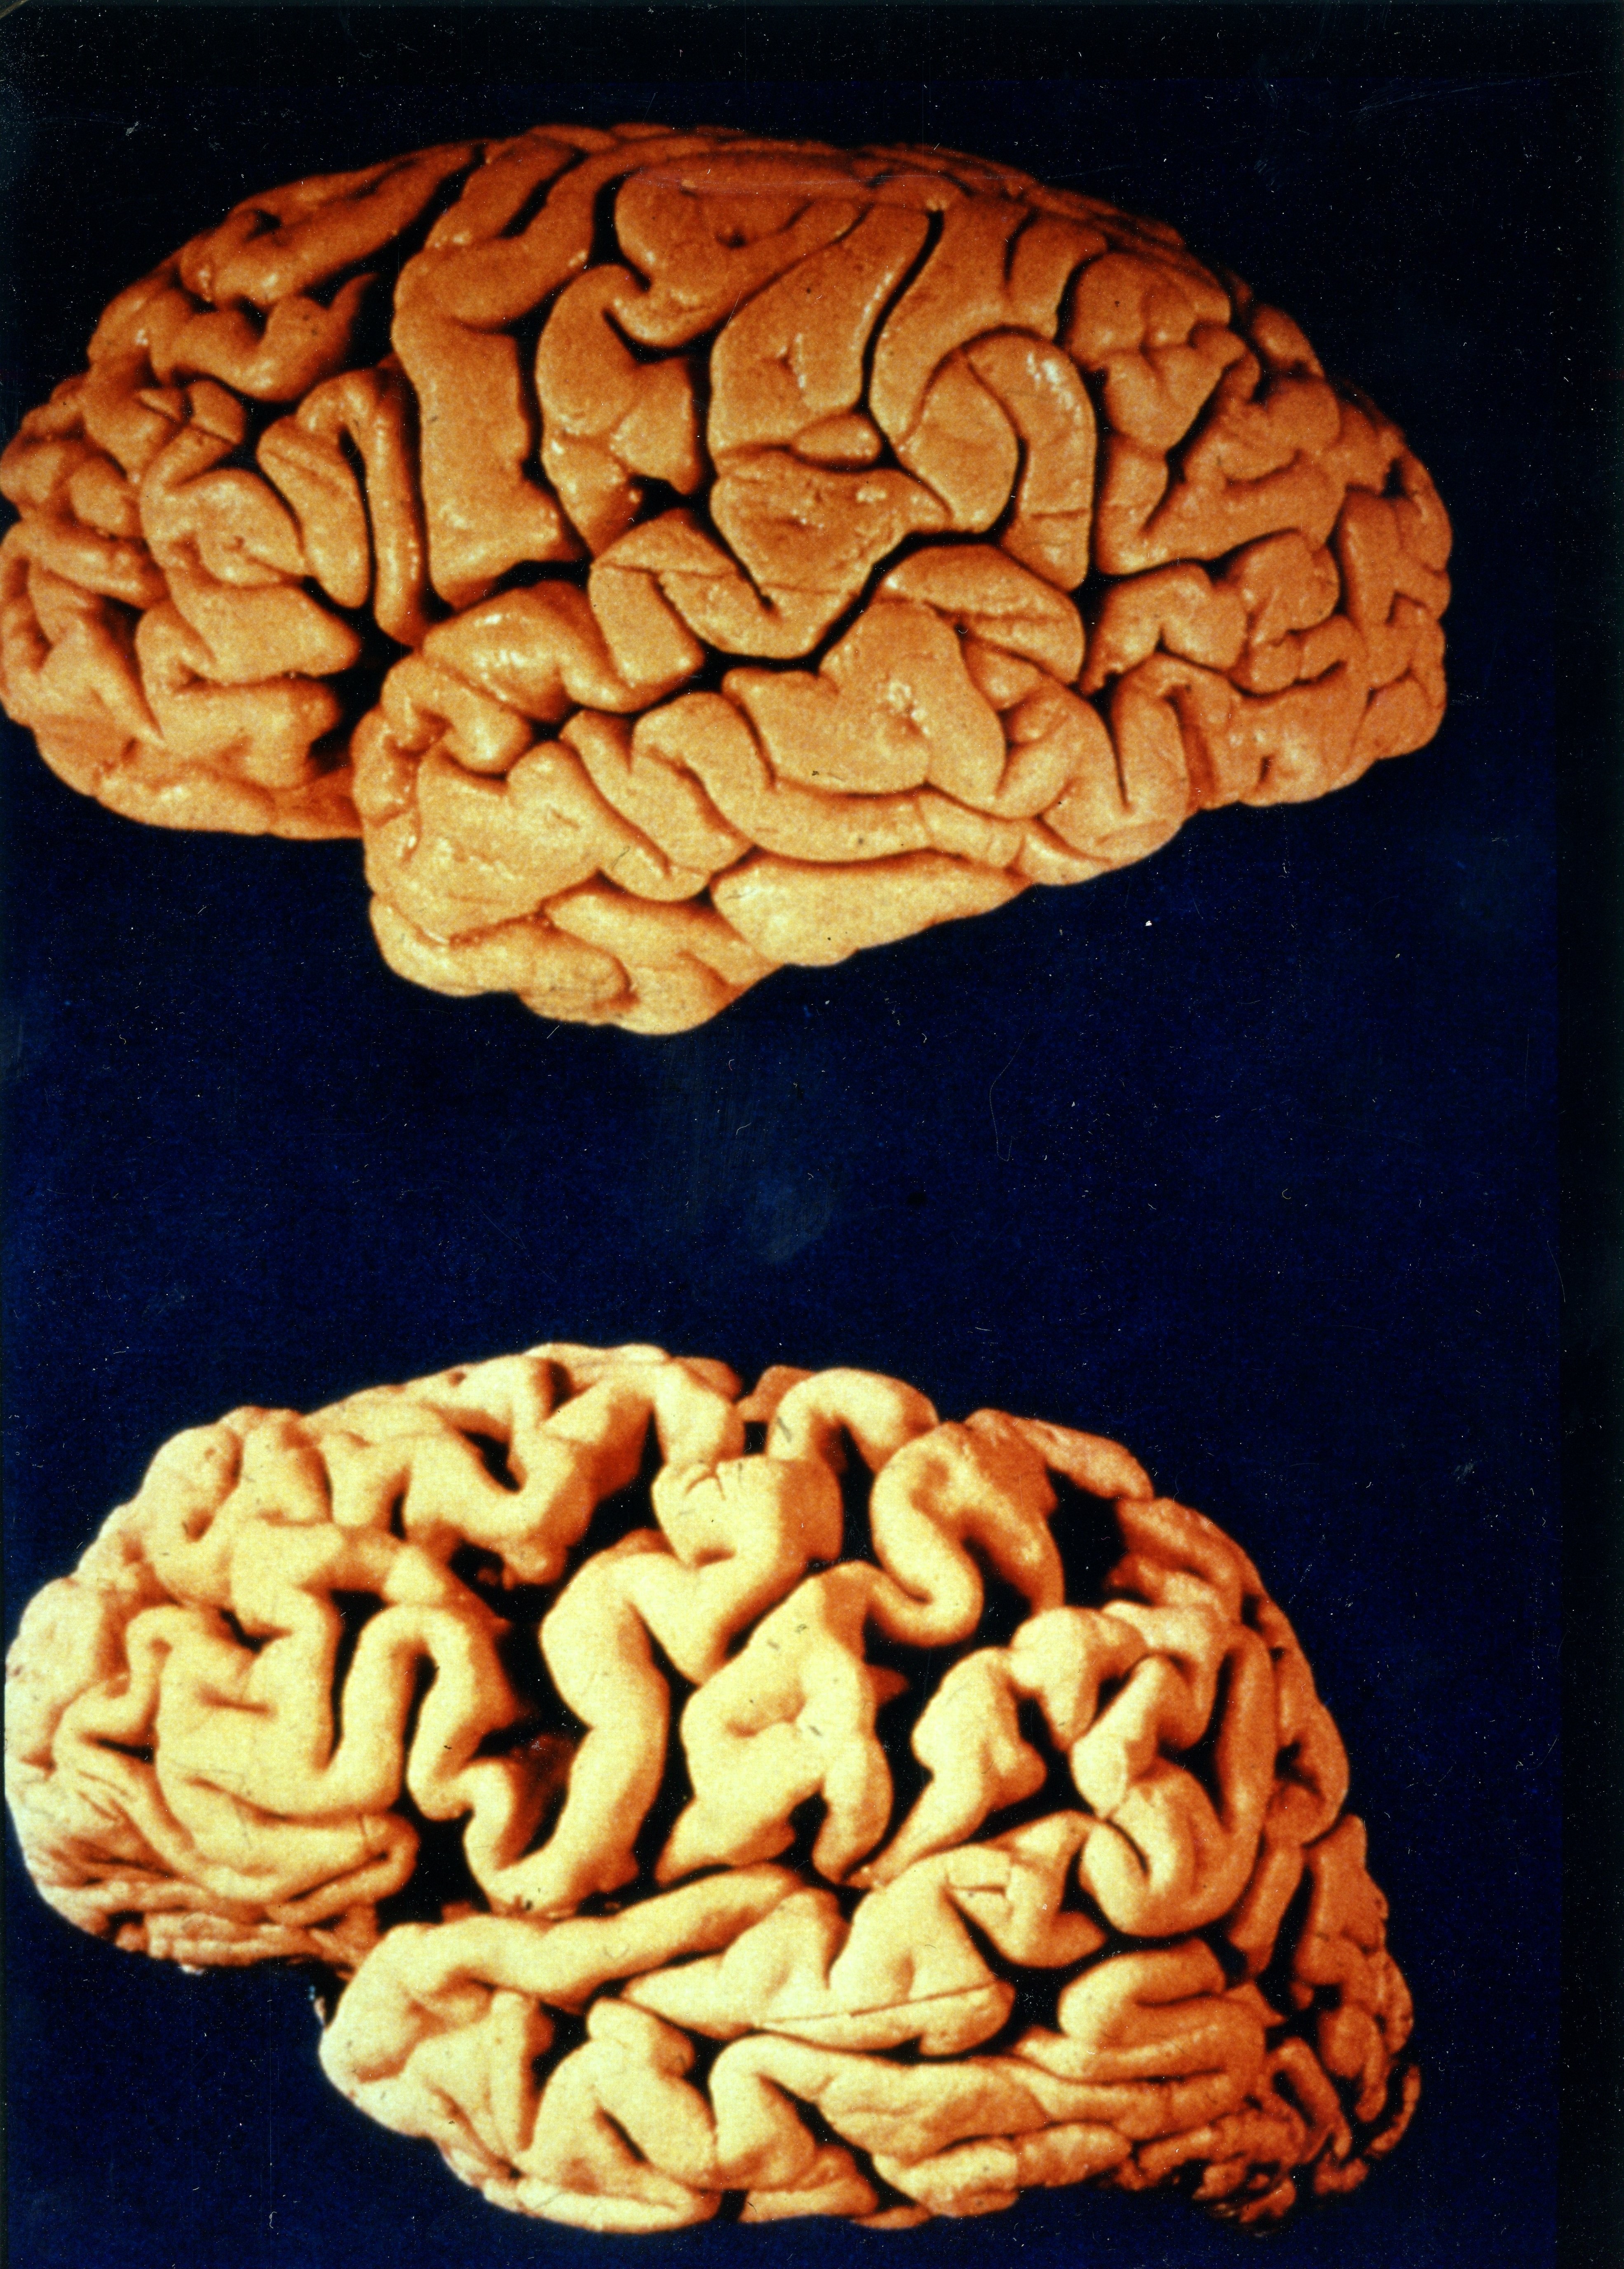

Zum Ende des Jahres 2023 lebten in Deutschland rund 1,8 Millionen Menschen mit Demenz. Häufigste Demenzursache ist die Alzheimer-Krankheit. Im Jahr 2023 sind etwa 400.000 Menschen im Alter 65+ neu an einer Demenz erkrankt. Etwa zwei Drittel davon werden in der häuslichen Umgebung von Angehörigen betreut und gepflegt. Infolge des demographischen Wandels nimmt die Anzahl der Betroffenen weiter zu. Gelingt kein Durchbruch in Prävention oder Therapie, könnten nach aktuellen Schätzungen in Deutschland im Jahr 2050 bis zu 2,7 Millionen Menschen im Alter 65+ erkrankt sein.